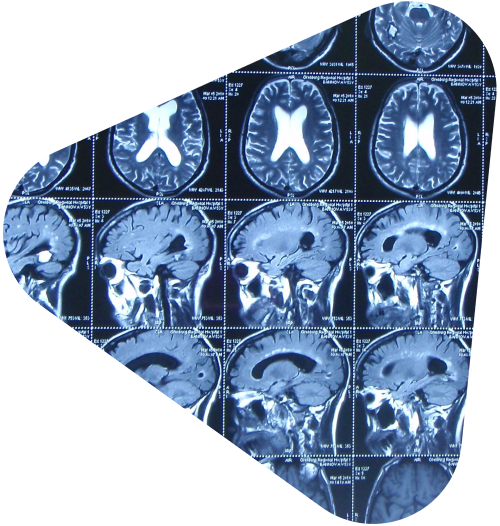

Процесс постановки диагноза по результатам МРТ включает несколько этапов. Сначала врач-рентгенолог или специалист по лучевой диагностике проводит расшифровку полученных снимков. Эти снимки демонстрируют изменения в тканях, наличие аномалий, воспалительных процессов, новообразований и других патологий. На основании анализа изображений и медицинской истории пациента специалист формирует окончательное заключение.

При исследовании головного мозга с помощью МРТ можно обнаружить такие патологии, как инсульты, рассеянный склероз, опухоли, травматические повреждения и инфекции. В области позвоночника метод позволяет выявить протрузии и грыжи межпозвоночных дисков, сдавления нервных корешков и дегенеративные изменения позвонков.